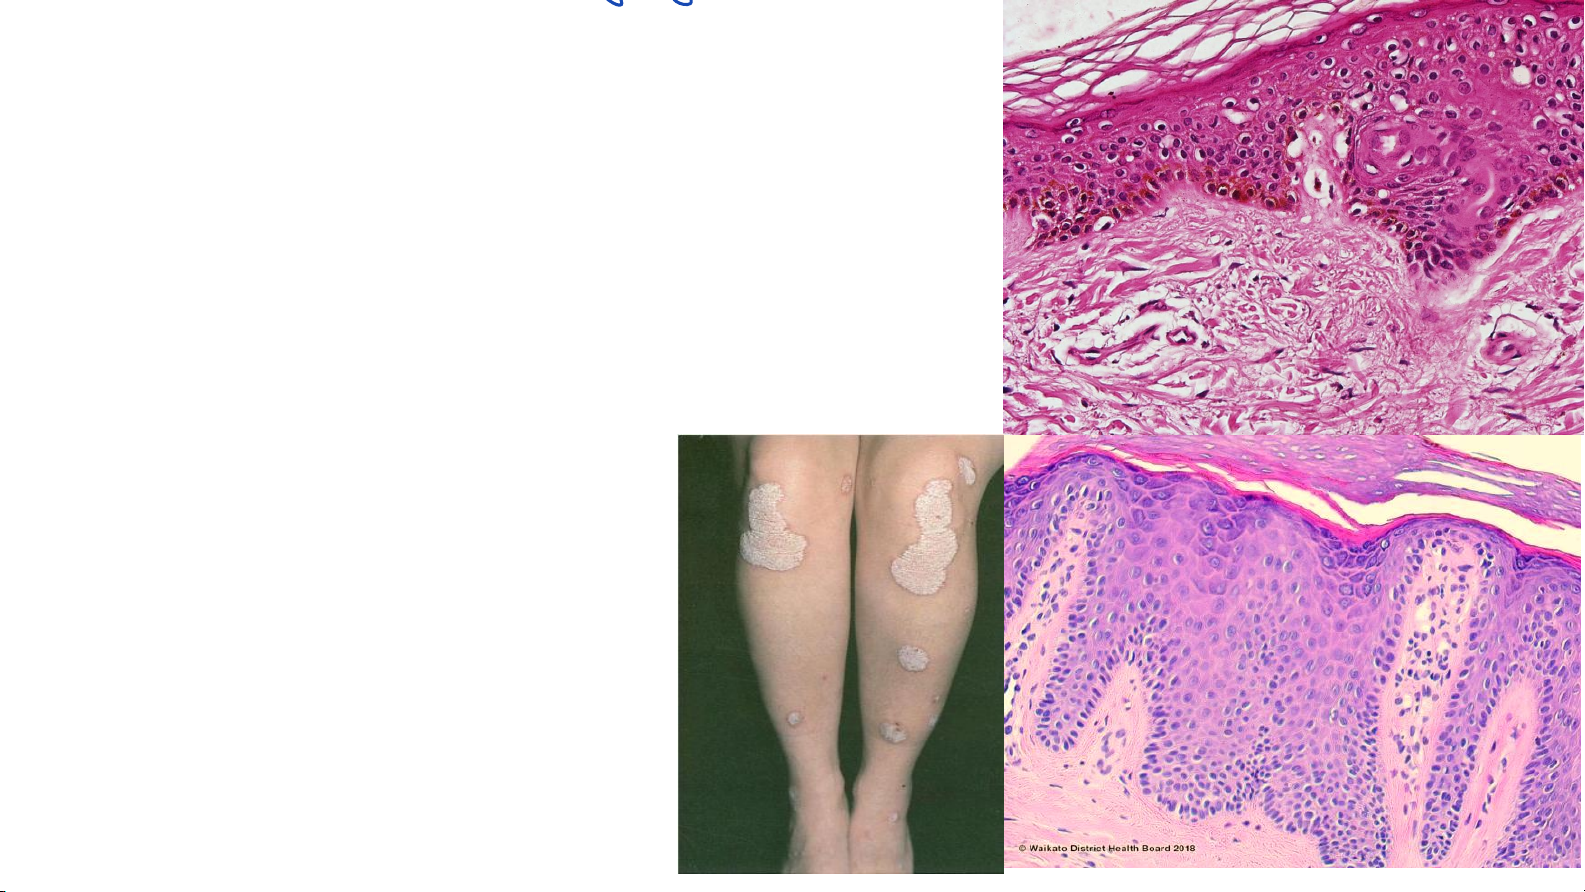

chất sựdàylên từng KOgâyđau • Chai chân ỵ • Mắt cá q bệnhlý lòngbànchânAy hiệntưagtăngnàng Tăng sừng tỹwlaugờấá 17 thàyđan gag Vảy nến

• Bệnh da sẩn vảy, mãn tính

• Quá trình biệt hóa: 3-5 ngày • Tăng sừng • Hiện tượng á sừng • Tăng gai • Mất hạt • Gờ bì dài

• Thấm nhập Neu, vi abces Munro

Histology and cell biology Abraham 4th 18 TB sắc tố (melanocyte)